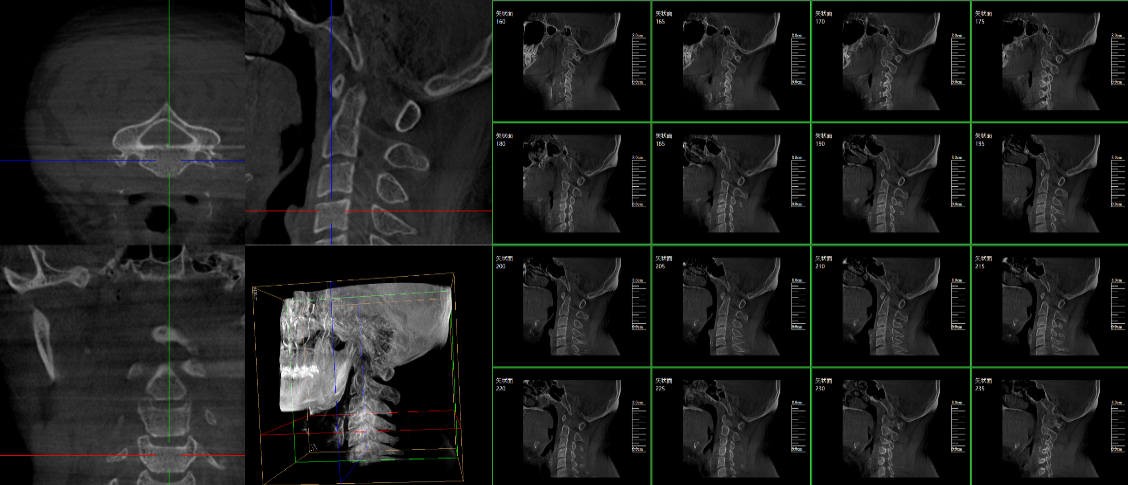

三维C臂,作为“术中CT”,能在术中快速地生成横断面、矢状面、冠状面和可旋转的立体图像,给术者提供360°无死角的观察角度,全方位准确判断骨组织和植入物的情况,为手术的实施提供保障,极大提高手术成功率,减少并发症概率。主要适用于骨科、脊柱外科、矫形外科、创伤骨科及手术室等。

普爱医疗三维C形臂具备术中实时三维成像,术中三维成像和横断面图像提供多角度的手术诊断信息,辅助医生进行术中评估判断,诸如骨折复位情况和内植入螺钉的尺寸和位置,辅助手术更好地完成;三维成像视野大,提供更大的术中三维成像视野,采集更多图像信息,可一次拍全全段颈椎、全段腰椎、七节胸椎、双侧骶骼关节、股骨头及单侧盆骨等。如果您想了解更多普爱三维C形臂优点及技术参数,欢迎咨询我们。